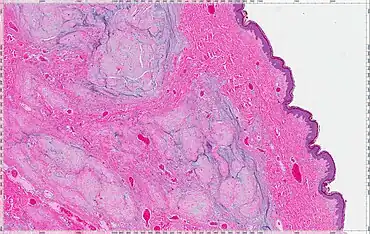

| Micrograph of an atrial myxoma. H&E stain. | |

| Myxoma | Margin | Vascular pattern | Cellularity | Stroma | Staining characteristics | Recurrence rate | Image (see Histology) |

| Cutaneous myxoma or Superficial angiomyxoma | Poor to moderately circumscribed, multilobular | Scattered thin-walled vessels | Moderately cellular, bland spindled and stellate cells, variable inflammatory cell infiltrate | Abundant mucin with clefts. Up to 30% have an associated epithelial component | Vimentin; variable staining with CD34, factor XIIIA, SMA1, MSA2 and S-100 | 20–30% |  |

| Intramuscular myxoma | Poorly circumscribed merges with surrounding muscle | Hypovascular variant; hypervascular variant | Hypocellular variant; hypercellular variant; bland spindle cells | Abundant mucin with cystic spaces. Hypercellular variant has strands of collagen | Vimentin; variable staining with actin, desmin, CD34 | None | |

| Juxta-articular myxoma | Poorly circumscribed infiltrates surrounding tissue | Focally vascular | Focally hypercellular, peripheral spindle cells with occasional atypical cells and mitoses | Abundant mucin, 89% of cases contain cystic spaces lined by fibrin or collagen | Vimentin; variable staining with actin, desmin, CD34 | 34% | |

| Aggressive angiomyxoma | Infiltrative | Uniformly distributed medium-sized blood vessels often with prominent hyalinization | Low to moderately cellular, evenly distributed round, spindled or stellate cells | Loose myxoid to focally collagenous | Vimentin, desmin, SMA1, MSA2, estrogen and progesterone receptor | 36–72% | |

| Angiomyofibroblastoma | Well circumscribed | Abundant thin-walled blood vessels | Alternating hypercellular and hypocellular areas, perivascular condensations of spindled to epithelioid stromal cells | Collagenous to edematous with minimal mucin | Vimentin, desmin, CD34, estrogen and progesterone receptor | No recurrences reported, but rare cases of sarcomatous degeneration | |

| Superficial acral fibromyxoma | Pushing to infiltrative | Mild to moderately accentuated vasculature | Moderately cellular, spindle and stellate cells with a storiform to fascicular pattern, variable mast cells | Myxoid to collagenous | CD34, EMA3, CD99 | Recurrence rare and primarily for incompletely excised lesions | |

| Neurothekeoma (Nerve sheath myxoma) | Well circumscribed, multilobular | Hypovascular | Moderately cellular, spindled cells in fascicles and whorls | Nests of cells separated by collagenous bundles | S-100, EMA3 | 47% if incompletely excised |